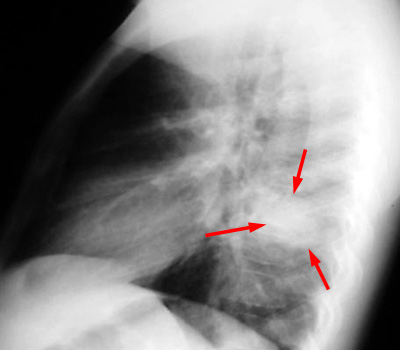

| Example of a "round pneumonia." PA and LAT CXR shows a round opacity in the superior segment of the right lower lobe which has the appearance of a mass. |